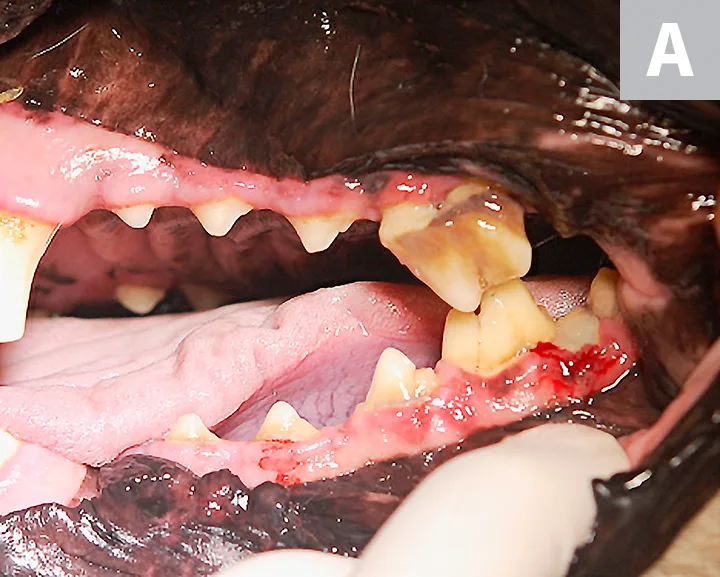

Intraoral image (A) and close-up view (B) of the left maxillary fourth premolar showing signs of advanced periodontal disease. Gingivitis, gingival recession, furcation involvement of the left maxillary fourth premolar, and gingivitis of the third and fourth mandibular premolars and the first mandibular molar can be seen.

Oral examination confirmed an unhealed extraction site of the right maxillary fourth premolar with a root fragment protruding into the oral cavity. Periodontal disease of the left maxillary fourth premolar (Figure 2) and a complicated crown fracture of the right maxillary canine (Figure 3) were also identified.